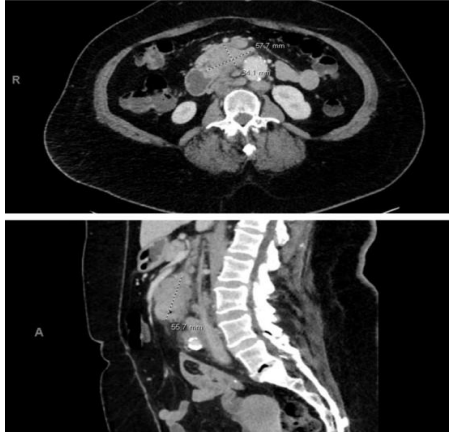

CT scan of the abdomen/pelvis (Figure 1) revealed a heterogeneous mass measuring approximately 5.8 x 3.4 x 5.6 cm involving the third portion of the duodenum and pancreatic head with subjacent enlarged lymph nodes. It also revealed several hypodense-like masses scattered throughout the liver

Figure 1: CT abdomen/pelvis showing 57.7mm mass in the third portion of the duodenum. In the transverse view, the mass measures 57.7mm x 34.1mm in size. It abuts the pancreas. The sagittal view shows a heterogeneous mass with irregular borders with the longest diameter of 55.7 mm.